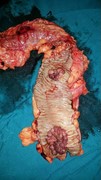

Synchronous adenocarcinoma and neuroendocrine carcinoma of the colon: a case report

Sonmoon Mohapatra and others

Journal of Surgical Case Reports, Volume 2016, Issue 3, March 2016, rjw042, https://doi.org/10.1093/jscr/rjw042